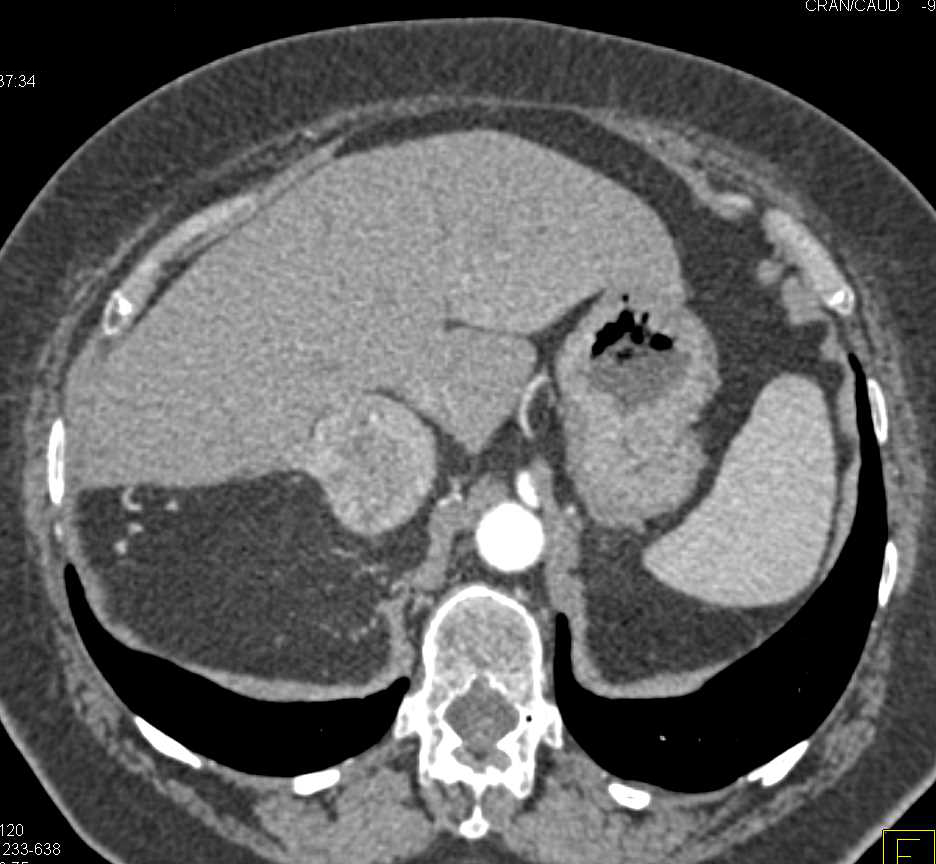

Right Adrenal Hematoma